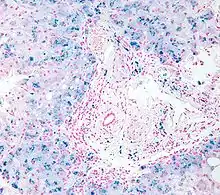

Cerebrospinal fluid specimen stained with Perls Prussian blue showing iron containing macrophage (stained blue) surrounded by erythrocytes (stained red)

In histology, histopathology, and clinical pathology, Perls Prussian blue is a commonly used method to detect the presence of iron in tissue or cell samples.[1]:235[2][3][4] Perls Prussian Blue derives its name from the German pathologist Max Perls (1843–1881), who described the technique in 1867.[2] The method does not involve the application of a dye, but rather causes the pigment Prussian blue to form directly within the tissue.[5] The method stains mostly iron in the ferric state which includes ferritin and hemosiderin, rather than iron in the ferrous state.[6]

Perls's method is used to indicate "non-heme" iron in tissues such as ferritin and hemosiderin,[6] the procedure does not stain iron that is bound to porphyrin forming heme such as hemoglobin and myoglobin.[2] The stain is an important histochemical stain used to demonstrate the distribution and amount of iron deposits in liver tissue, often in the form of a biopsy.[6][7] Perls's procedure may be used to identify excess iron deposits such as hemosiderin deposits (hemosiderosis) and in conditions such as hereditary hemochromatosis.[8] Perls Prussian blue is commonly used on bone marrow aspirates to indicate levels of iron storage[4] and may provide reliable evidence of iron deficiency.[7]